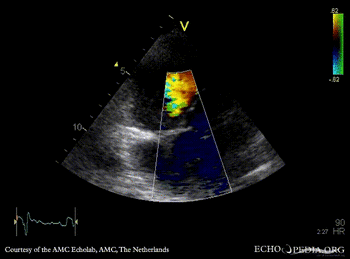

| TEE: muscular VSD